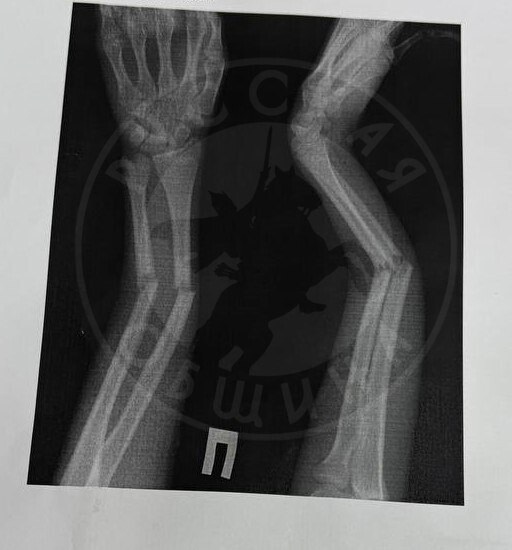

5 февраля 2025 года в школе № 6 г. Нижнекамска ученик 6-го класса нанес тяжёлую травму своей однокласснице. По словам пострадавшей, мальчик подошёл к ней и спросил: «Тебя когда-нибудь брали на прогиб?». После её отказа вступать в разговор он схватил её за руку, дёрнул на себя и бросил на пол. В результате девочка получила закрытый перелом обеих костей правого предплечья, сильный эмоциональный стресс. Ей потребовалась срочная операция под общим наркозом. Врачи не исключают, что для восстановления потребуется установка аппарата Илизарова и длительная реабилитация.